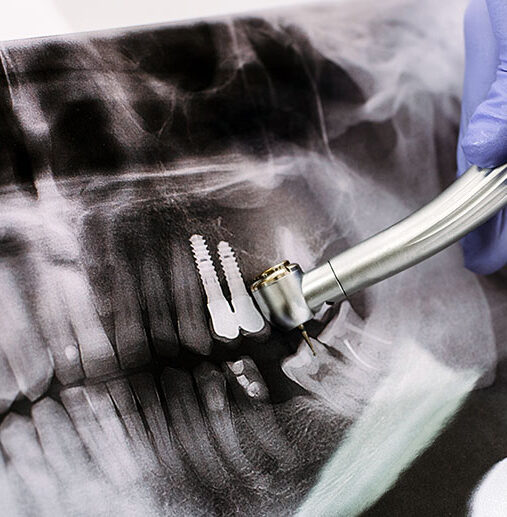

İmplant Uygulamaları

İmplant Uygulamaları Diş çekimi/kaybı sonrası komşu dişlerin korunması, ilgili kemik bölgesinde minimal erimeye